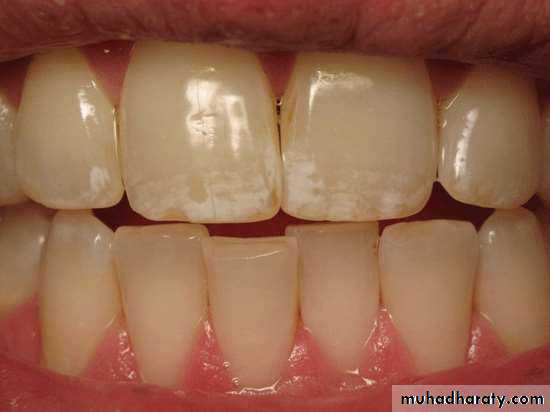

VERY MILD (1) Small, opaque, paper

white areas scattered irregularly overthe tooth , but not involving as much as

approximately 25% of tooth surface.

Frequently included in this

classification are teeth showing no

more than about 1-2 mm of white

opacity at the tip of the summit of the

cusps of bicuspids or second molars.

MILD (2)The white opaque

areas in the enamel ofteeth are more extensive

but do not involves as

much as 50% of tooth